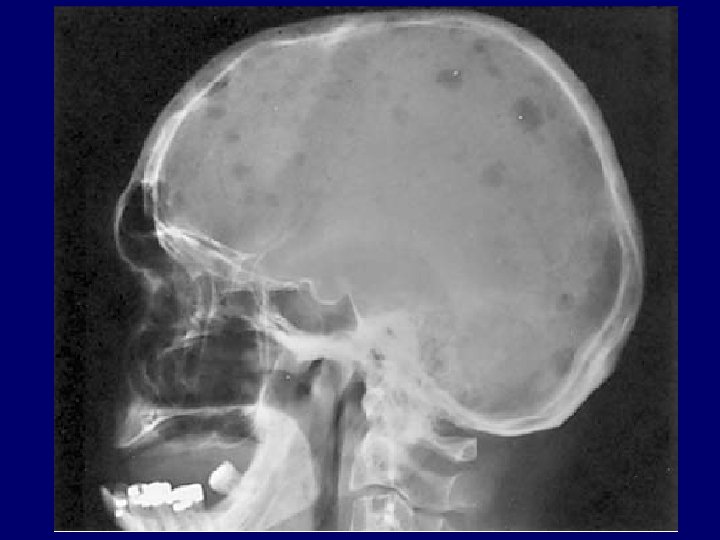

Multiple Myeloma • malignant proliferation of plasma cells • tumor, its product, host response

Multiple Myeloma • malignant proliferation of plasma cells • tumor, its product, host response --> bone pain or fracture, renal failure, susceptibility to infection, anemia, hypercalcemia, clotting abnormality, neurologic symptoms, hyperviscosity syndrome • rare under 40 year of age, male, black